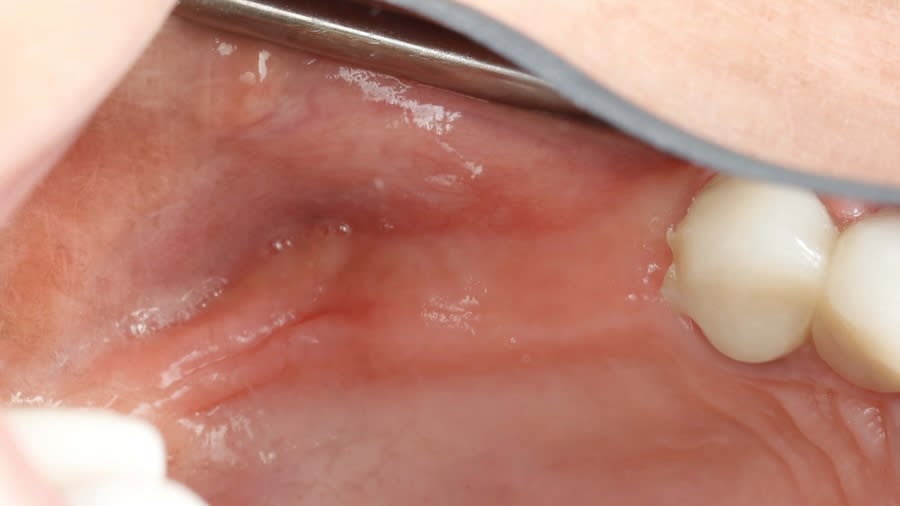

Step 1: Measure bone height at the osteotomy site on the CBCT. Measure ridge clinical width. A minimum of 7 mm alveolar ridge width is needed. Perform horizontal incision 2 mm to 3 mm palatally from the planned osteotomy site and elevate the flap using regular techniques of the clinician’s choice.

Step 3: Graft placement: Once the final osteotomy/lift is reached, it is suggested to place one platelet-rich fibrin (PRF) membrane (cut into three smaller pieces) or two wet soft hemostatic sponges to be pushed gently with the Densah bur (5.0) before introducing well-hydrated particulate allograft or biomaterials.

Use same Densah bur VT4555 (5.0) with Vertical Stop in the CCW motion at low speed (100 RPM) without irrigation and gently advance it 1 mm to 2 mm to propel the allograft into the sinus. Repeat the graft compaction step to achieve further elevation of the sinus membrane. Keep propelling well-hydrated allograft or other biomaterial until achieving adequate grafting volume. Achieve full adequate flap primary closure.

Step 4: Allow 4 to 6 months for the sinus graft healing. CBCT evaluation is needed to evaluate the available regenerated bone height for the implant placement. Reflect soft tissue utilizing standard surgical instruments, and use Densah burs for osseodensification site preparation to prepare the implant osteotomy and place the implant.

Case 1 (Figure 3 through Figure 24) depicts a 3-year follow-up of combined osseodensification sinus protocol IV in a severely resorbed maxillary ridge with ≤0.5 mm bone height in molar sites and horizontal deficiency at the first premolar site, using a two-stage approach for implant placement.